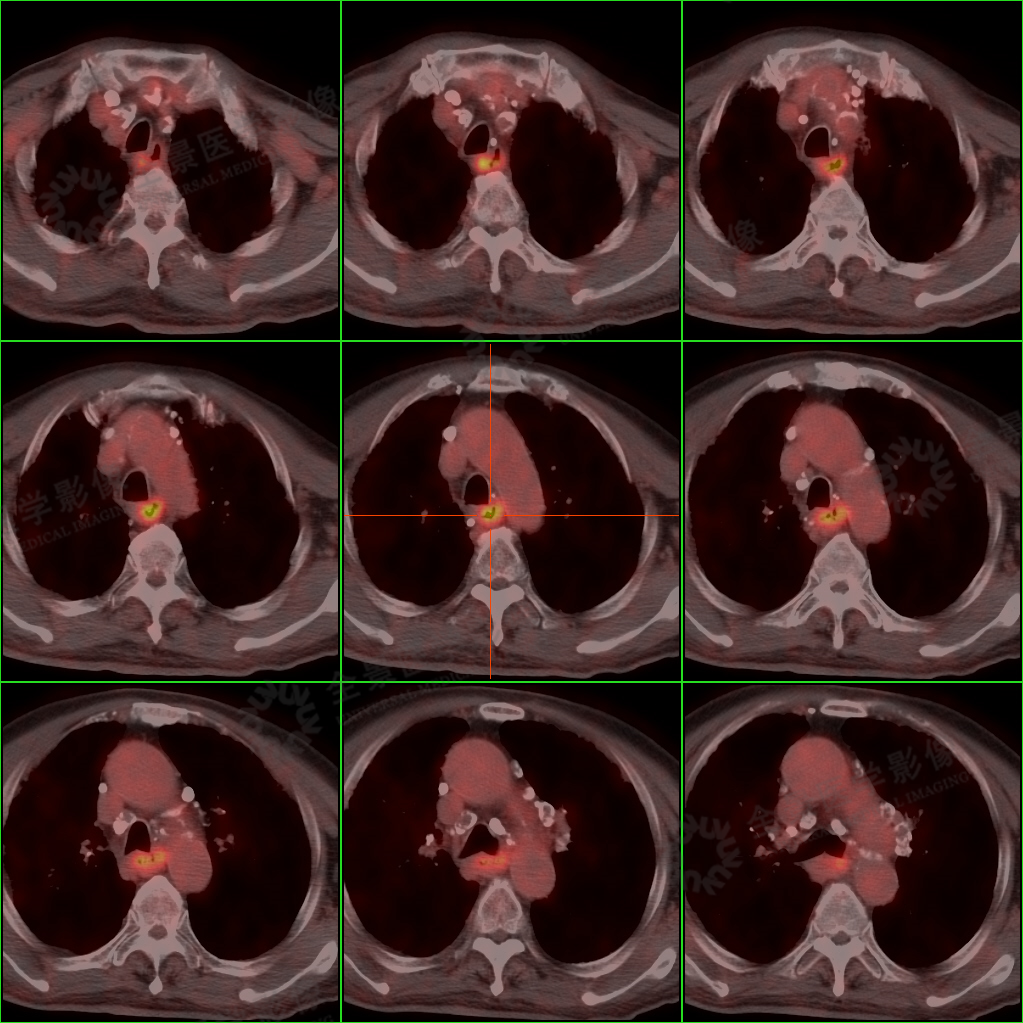

PET/CT 检查图像:

PET/CT 检查显示: 陈老师食管胸中段壁增厚、毛糙,FDG 摄取增高,考虑食管癌可能,建议进一步通过胃镜活检明确诊断。